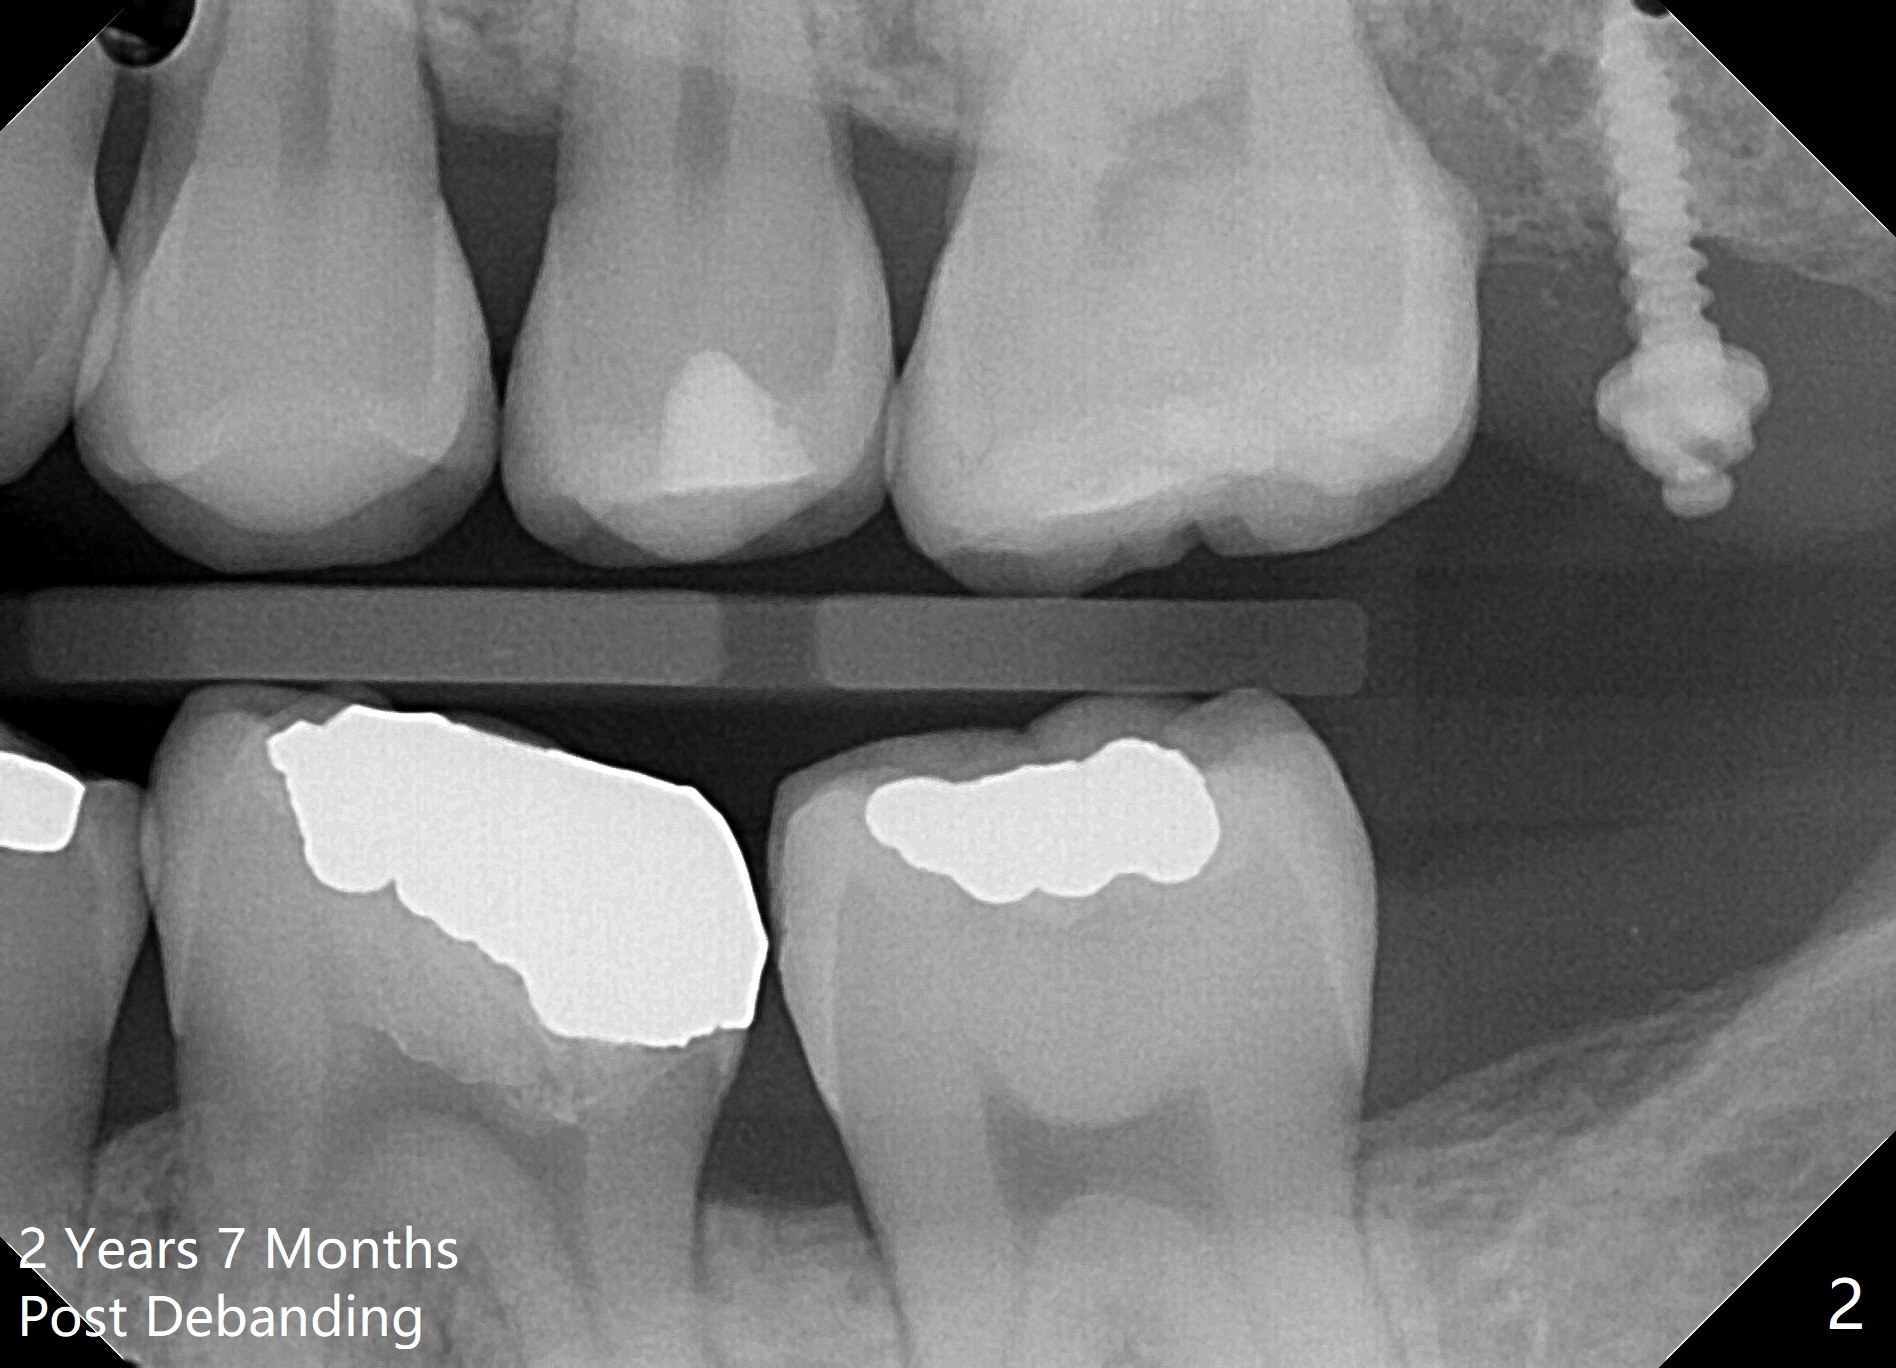

2 Years 7 Months Post Debanding

Return to Ortho Cases 植牙,导板与正畸 Five months post debanding 3 Years Post Debanding